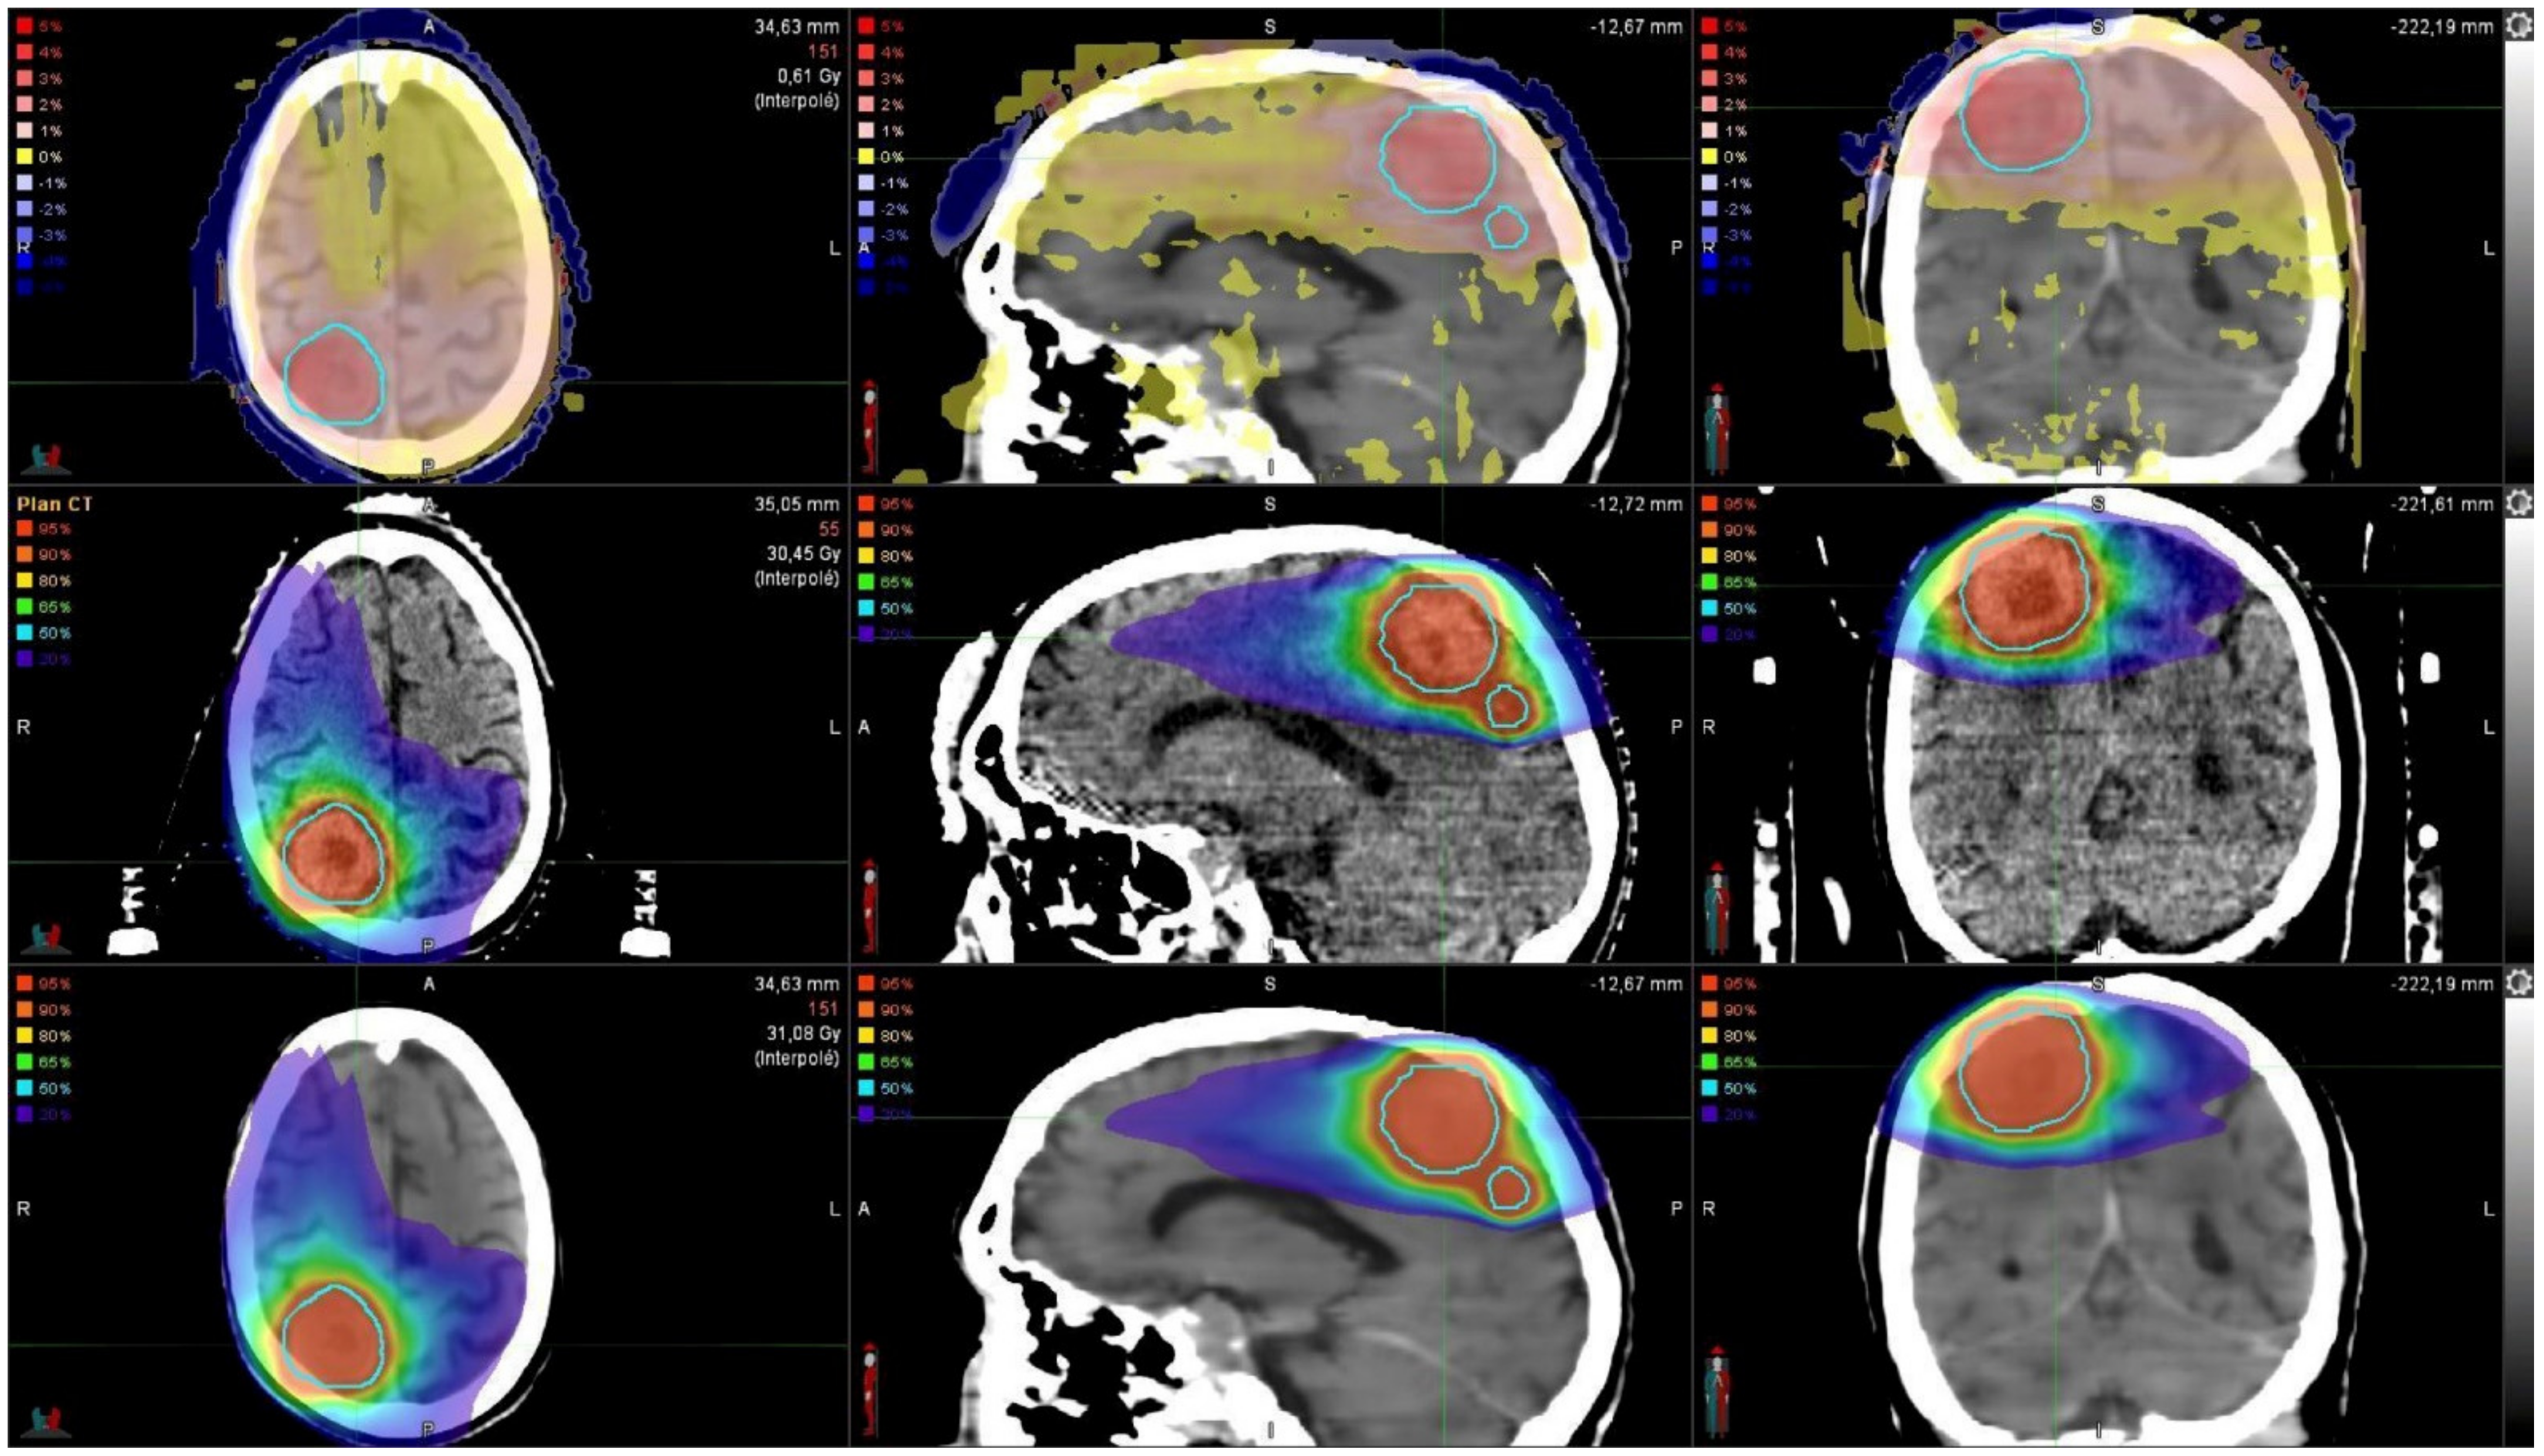

2.3. Treatment Planning

2.5. Dose Calculations

3.4. Local and Global Gamma Analysis